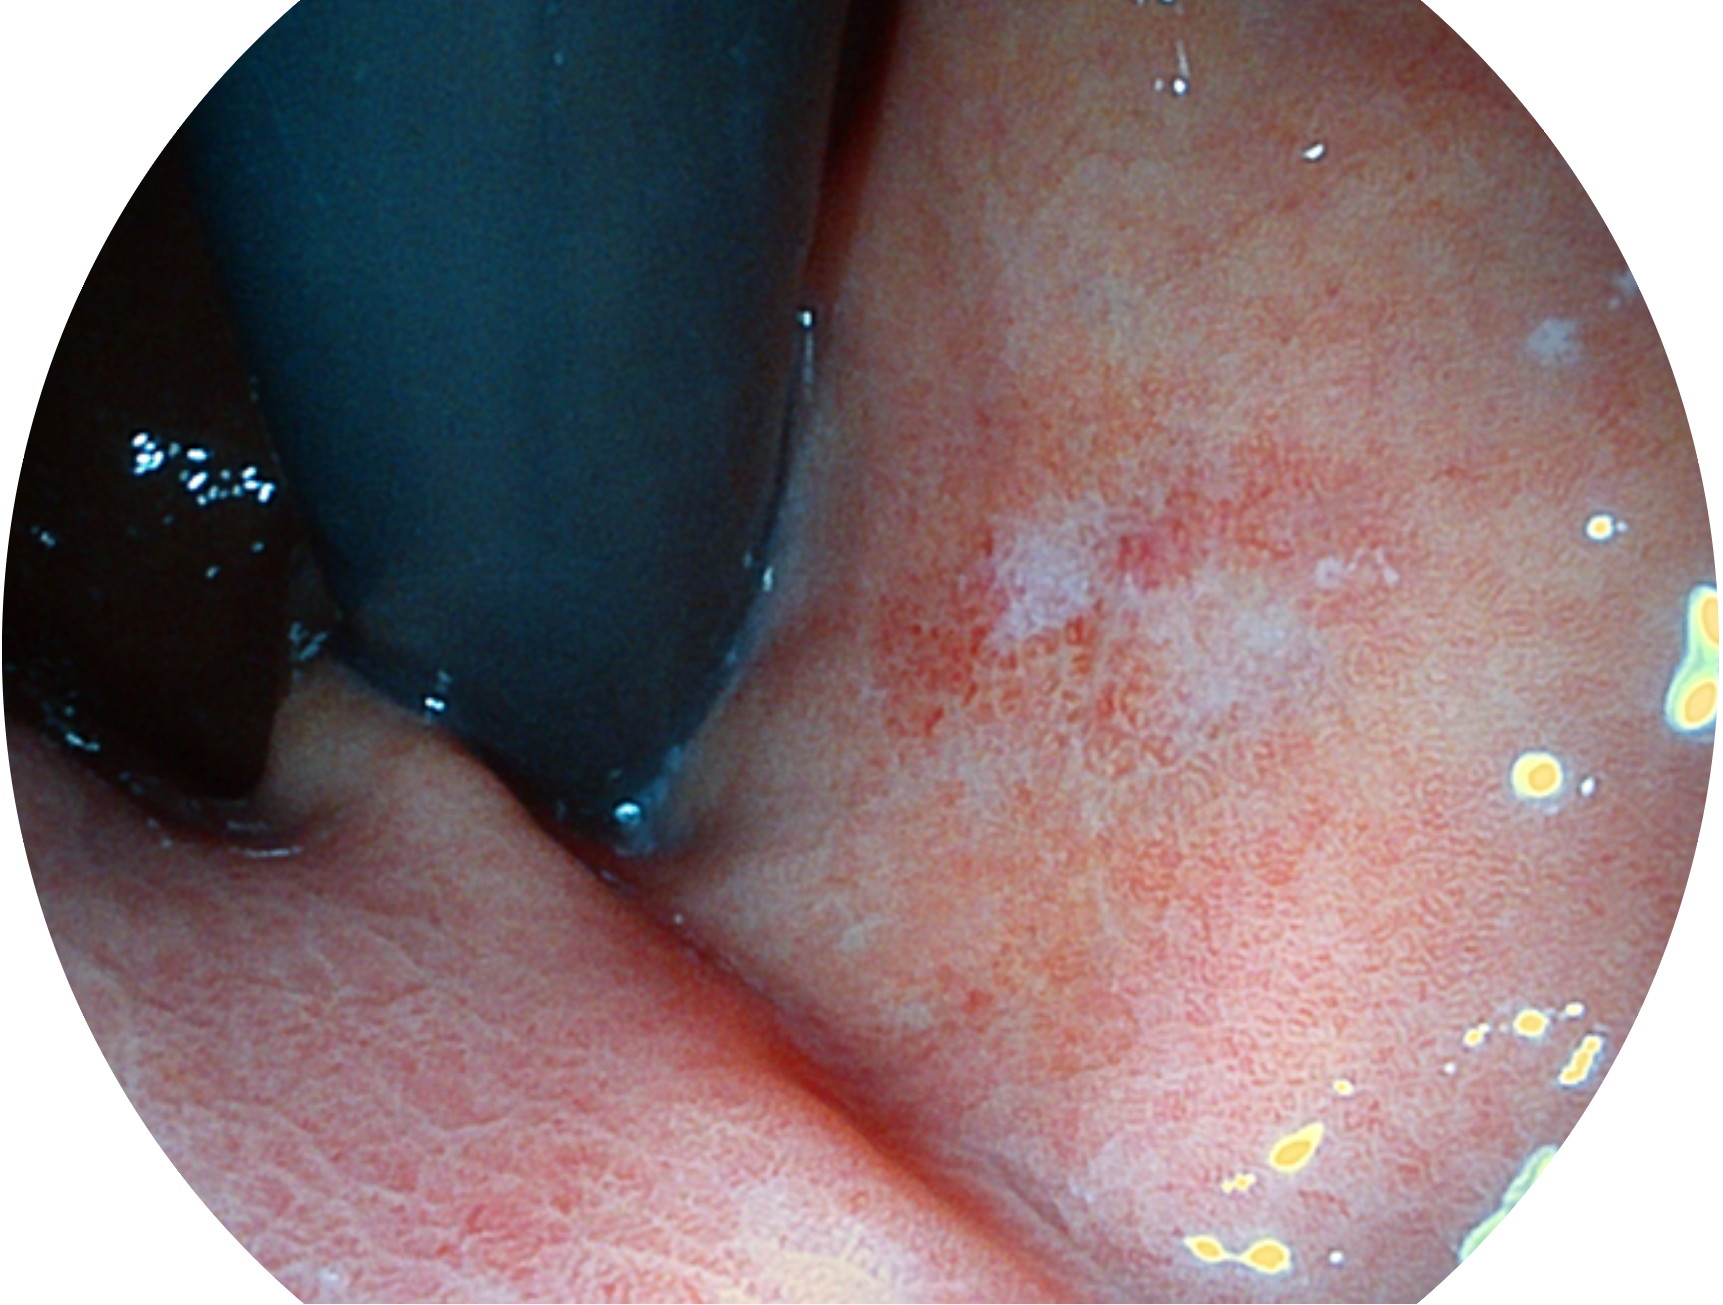

milan米兰新开发的内镜染色技术,主要是基于多波长LED 光源的开发,VLS-55Q 四波长LED 光源是由四个不同颜色的LED光按照相应照明模式所规定的特定发光比例进行合束后形成,合束后形成的照明光的光谱由红光、绿光、蓝光及蓝紫光这四个不同的波段范围构成。具有更高光谱自由度,通过光谱比例的控制,实现了聚谱成像技术,英文全称为“Spectral Focused Imaging, SFI”,缩写为“SFI”和光电复合染色成像技术,英文全称为“Versatile Intelligent Staining Technology, VIST”,缩写为“VIST”。